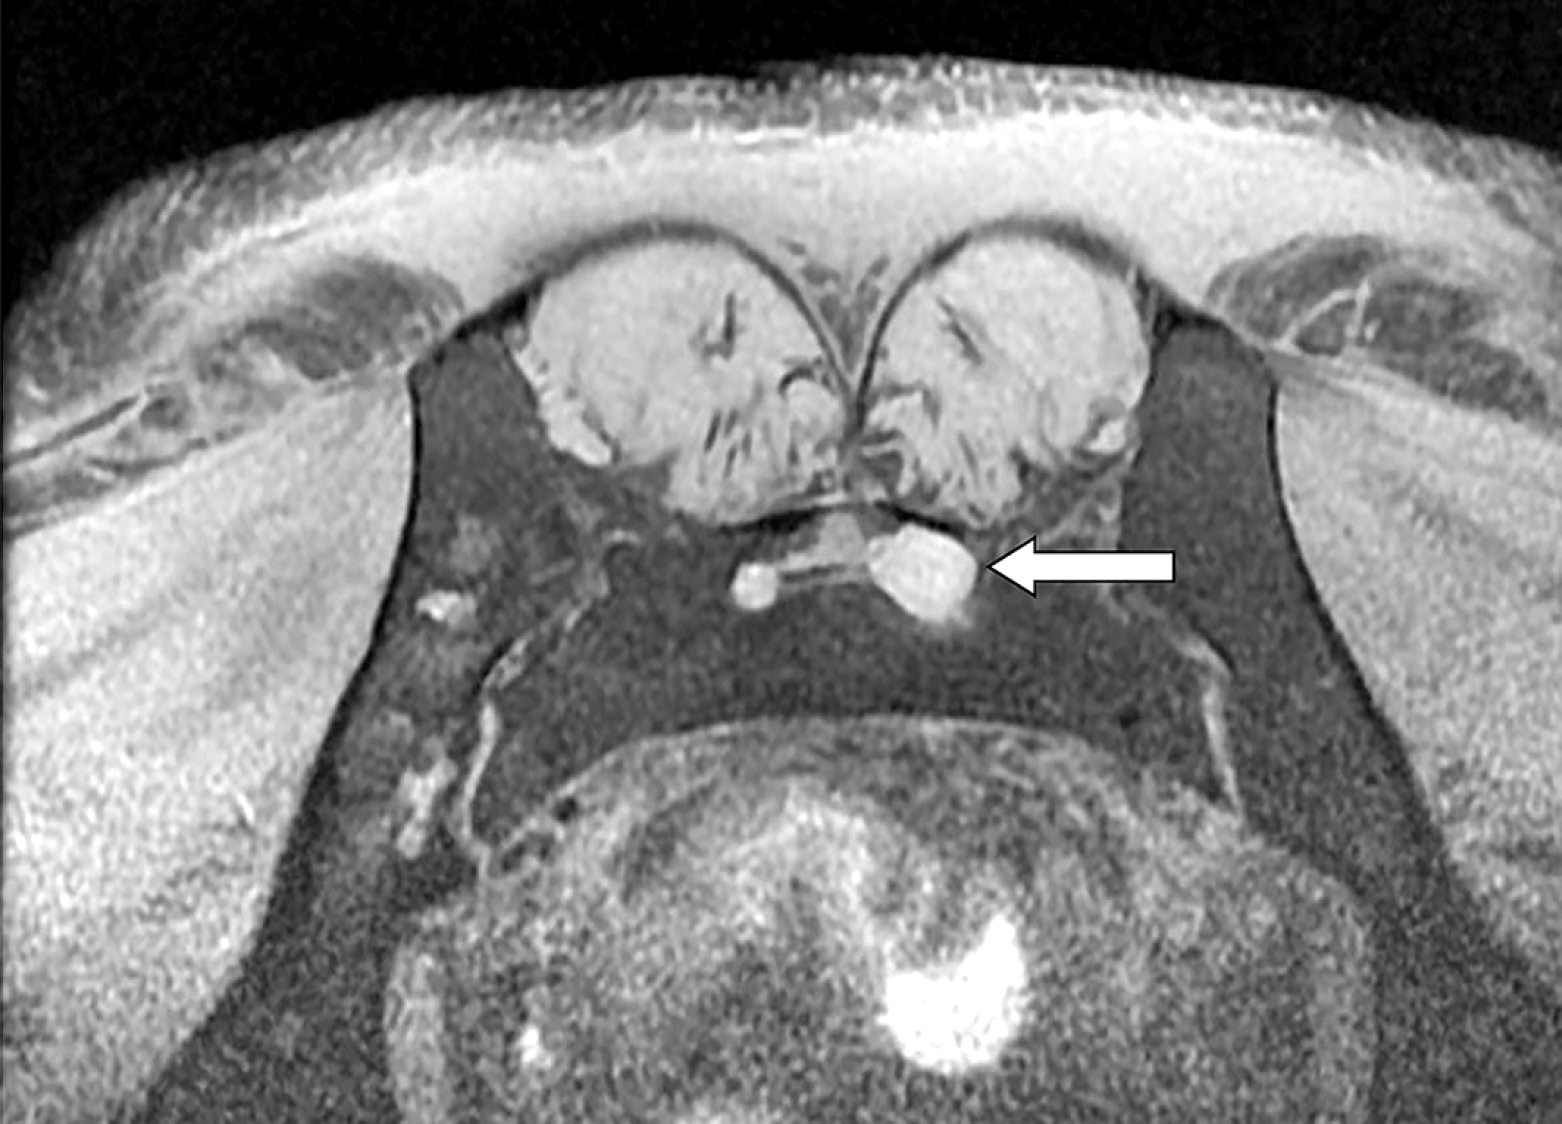

Учитывая данные МРТ, причиной интенсификации боли могло стать прогрессирование основного заболевания, которое проявилось в виде поражения периферической нервной системы (выявлено образование корешка на уровне S2 позвонка слева (см. рис.)).

Поражение корешка на уровне S2 позвонка. По данным МРТ (режим Т1) в просвете крестцового канала слева выявляется локальное утолщение корешка 1,1 × 3,0 см с расширением крестцового отверстия и активным накоплением контрастного препарата с быстрым его «вымыванием»

S2 root lesion. According to MRI (modeT1) there is a local thickening of the root 1.1 × 1.3 cm in the sacral canal with widening of sacral foramen and active contrast accumulation and rapid «washing out»

Также по результатам МРТ выявлены задняя центральная грыжа диска L4-5 (3 мм) и диффузные задние протрузии дисков L2-3, L3-4 (до 1 мм), не влияющие на клиническую картину.